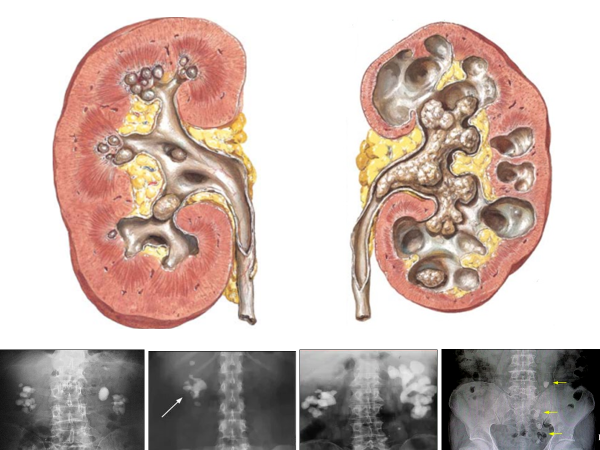

Мочекаменная болезнь (уролитиаз)

• Частота – 5-10% (до 20%) в популяции.

• Встречается в 3 раза чаще у мужчин.

• Наблюдается несколько чаще в правой почке.

• Камни почки могут быть одиночными и множественными.

• Двухсторонняя локализация наблюдается у 15-20% больных.

• Размеры – мелкие (<1 см), средние (1-2 см), крупные (>2 см).

• Нередко (в 3-30% случаев) камни выполняют всю чашечно-лоханочную систему – коралловидные камни (встречаются в 3 раза чаще у женщин).

• Наблюдается несколько чаще у женщин, особенно при коралловидном уролитиазе.

• Камни могут располагаться в почках (нефролитиаз - в верхней, средней или нижней группах чашек, в лоханке), в мочеточнике (уретеролитиаз - в проксимальном, среднем или дистальном отделах), в мочевом пузыре (цистолитиаз) и в уретре (уретролитиаз).

• Частота локализации в почках и мочеточниках составляет до 92%, в мочевом пузыре – до 7%, в уретре – около 1%.